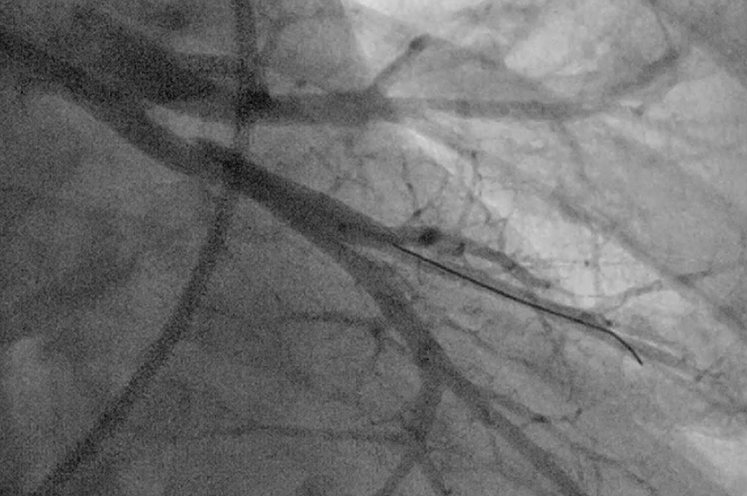

Interior lung image

Balloon pulmonary angioplasty (BPA) is a minimally invasive procedure performed in our cardiac catheterization lab.